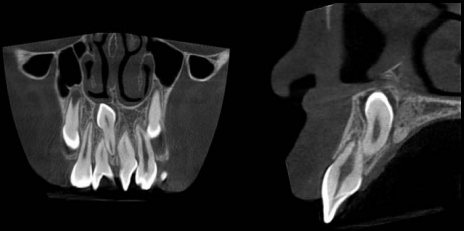

En la vasta mayoría de los casos, los dientes supernumerarios están impactados y sólo pueden ser visibles radiográficamente (12). La posición de los mesiodens normalmente es evaluada con estudios radiográficos, en la que se incluyen las radiografías periapicales, las oclusales y las ortopantomografías (figura 2), ya que facilitan el proceso de diagnóstico de mesiodens. Aunque las radiografías panorámicas son la mejor herramienta para el diagnóstico de los dientes supernumerarios, también pueden ser engañosas en algunos casos, ya que la claridad en la región de la línea media es limitada para el diagnóstico de los mesiodens. Para una visión más precisa en la región de los incisivos, también es útil la radiografía periapical anterior, y para mejorar la localización y cuando exista incertidumbre en el diagnóstico, la radiografía de tipo oclusal provee información útil en esta alteración. Con la técnica de paralelismo, se puede evaluar la posición bucolingual de los mesiodens no erupcionados (6,13,23,28). Hoy en día, el estudio de elección para el diagnóstico de los mesiodens es la tomografía conebeam (CBCT). El Conebeam provee información invaluable como la localización exacta y forma del mesiodens, incluyendo la relación que guardan con los incisivos centrales permanentes, con el potencial de superar la mayoría de las limitaciones técnicas de la proyección de película normal y la capacidad de proporcionar una representación tridimensional (3D) de alta resolución de los tejidos maxilofaciales de una manera rentable y eficaz en dosis. Actualmente se considera la mejor herramienta imagenológica de diagnóstico y es de gran ayuda para el plan de tratamiento cuando se requiere de la extracción del mesiodens (8,23,38). En los niños principalmente, se ha incrementado el uso de la CBCT para los dientes supernumerarios ya que nos ayuda a observan las estructuras anatómicas importantes para poder realizar un adecuado plan de tratamiento, sin dañar estructuras ni dientes adyacentes (figura 3) (35).

Al Programa de Fortalecimiento de la Calidad Educativa (PFCE), Dirección General de Educación Superior para Profesionales de la Educación-Secretaría de Educación Pública. Al Dr. Julián González García (Radiología y Diagnósticos Odontológicos) por las imágenes de la figura 3.